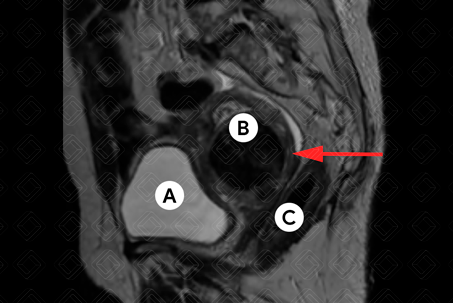

Descrição das figuras 1, 2, 3 e 4: Ressonância magnética da pelve feminina. Imagens pesadas em T2 nos planos axial e sagital (A = bexiga; B = útero; C = reto). Útero em retroversão, de contorno lobulado e sinal heterogêneo, por conta de nódulos miometriais, bem delimitados, hipointensos em T2, compatíveis com leiomiomas, destacando-se:

• Transmural, corporal posterior, medindo 5,0 x 4,8 x 4,6 cm (setas vermelhas à direita);

• Subseroso, corporal lateral direito, medindo 3,0 x 2,0 x 1,8 cm (setas vermelhas à esquerda).